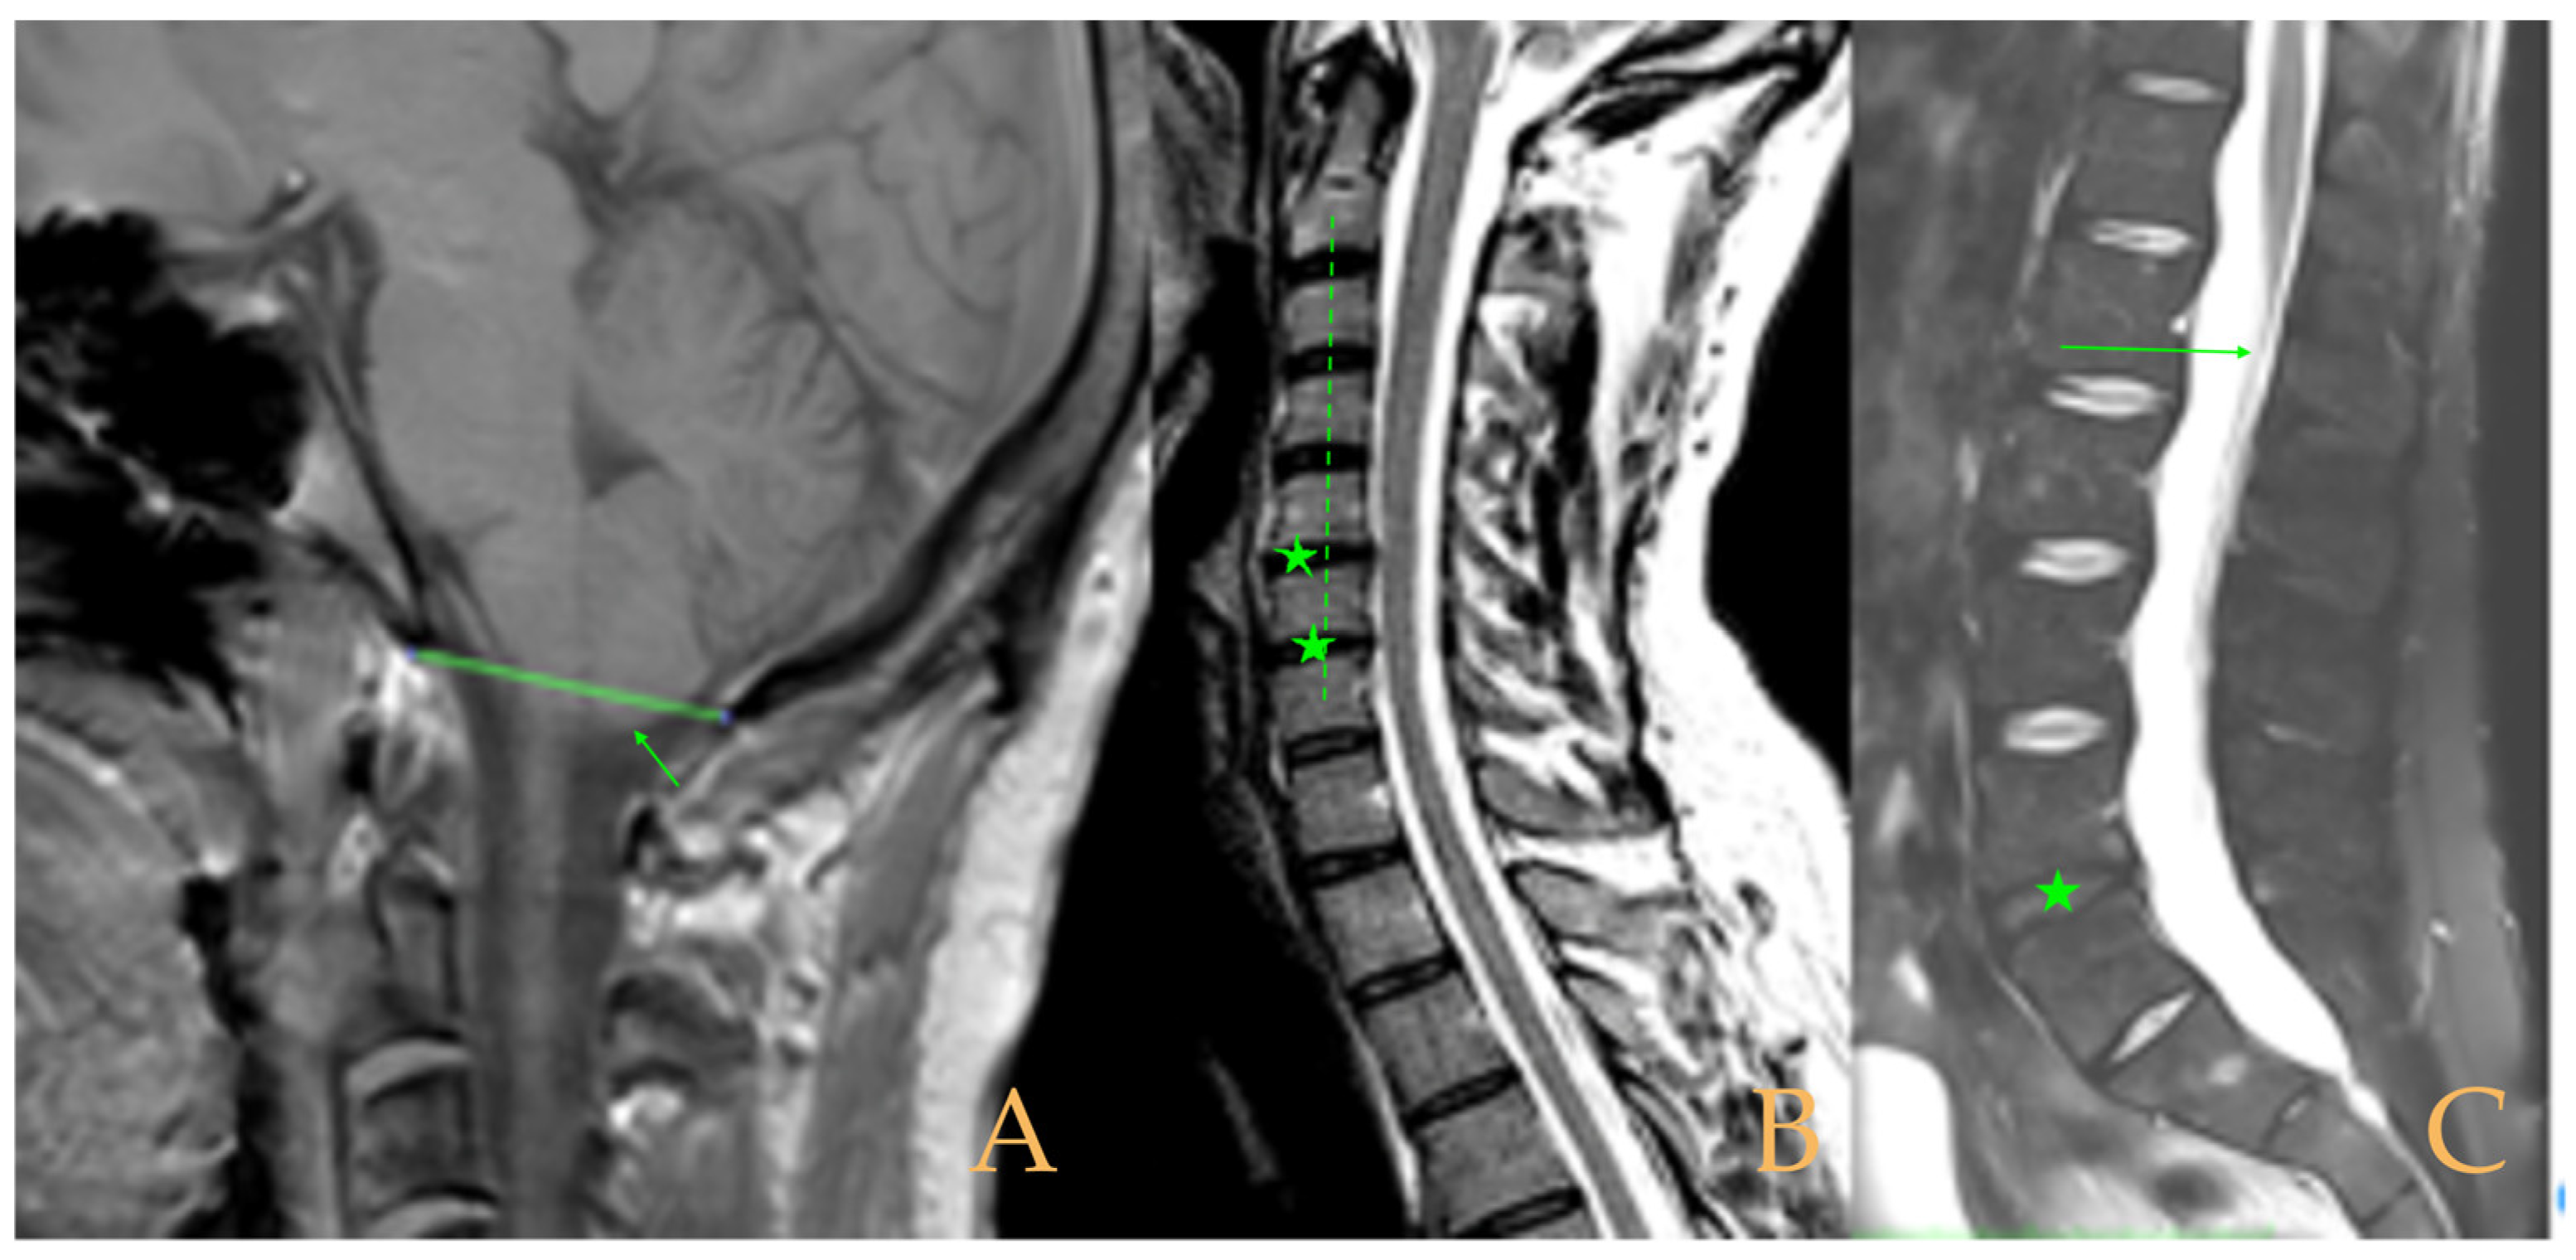

Impaction of the cerebellar tonsils was observed in the MRI. Increased supracerebellar space, incipient descent of the cerebellar tonsils and sinuous course of the optic nerves with oedema in the sheaths. Multiple protrusions, especially C5-C6 and C7-T1, straightening of the cervical spine, and a tense aspect of the cervical spinal cord. Discrete oedema in the cervical and thoracic spinal cord. The thoracic spine tends towards straightening. Low conus medullaris at the middle third of the L1 vertebra. Lumbarisation of S1 and visible filum terminale, somewhat thickened and tight (Figure 6). The full-spine X-rays revealed dextroconvex thoracic and lumbar scoliosis with very discrete minor compensatory curves in the upper and lower parts; straightening of the cervical spine and hyperlordosis of the lumbar spine; lumbarisation of S1; and rotoscoliosis of the lumbar spine from L5/S1 upwards (rotational subluxation).

Figure 6.

Imaging of patient 6. A: Increased supracerebellar space (short arrows), impaction of the cerebellar tonsils (star), and straightening of the cervical spine (interrupted line); image suggestive of medullar ischemia (long arrow), and B: conus medullaris at the level of the middle third of the L1 body (arrow).

The MRI showed descent of the cerebellar tonsils, 13 mm pineal cyst, and multiple disc protrusions in T4-T8 and T9-T10, with herniation T5-T6. Straightening of the thoracic and lumbar spine. Low conus medullaris at the upper third level of the L2 vertebra (Figure 7). The full-spine X-rays showed a mild double-curved thoracic and lumbar scoliosis (<10° Cobb), and lower extremity dysmetria with shortening of the left lower extremity estimated to be 3 mm at the level of the acetabular roofs and 7 mm at the level of the iliac crests. Dextroconvex lumbar scoliosis was estimated to be 2°, and levoconvex cervicothoracic scoliosis was estimated to be 10° (both total, including all vertebrae). The estimated lateral curves, including all vertebral bodies in each region, were cervical lordosis 25°, thoracic kyphosis 34°, and lumbar lordosis 53°.

Figure 7.

Imaging of patient 7. A: Descent of the cerebellar tonsils (star); B: straightening of the cervical spine (interrupted line) with image suggestive of medullar ischemia (arrow); and C: straightening of the upper part of the lumbar spine (interrupted line) and conus medullaris at the level of the upper third of L2 (arrow).

The MRI showed (Figure 9): descent of the cerebellar tonsils, ischemic foci in the white matter of the cerebral hemispheres, and oedema in the optic nerve sheaths. Kyphosis of the cervical spine (especially C5-C6-C7). Tense aspect of the cervical spinal cord. Disc disease: C3-C4-C5-C6-C7-T1. Ischemia and cervical and thoracic oedema. Straightening and scoliosis of the thoracic spine. Lumbar lordosis straightening. Conus medullaris at the level of the middle third of L1. Postsurgical changes in L4-L5 (disc prosthesis). The full-spine X-rays showed cervical, thoracic, and lumbar scoliosis, with the biggest curve being dextroconvex of wide radius in the thoracic and lumbar region.

Figure 9.

Imaging of patient 9. A: MRI of the posterior fossa, descent of the cerebellar tonsils (arrow), and increased supracerebellar space (star); B: straightening of the cervical spine (interrupted line) and suboccipital craniectomy with C1 laminectomy (star); and C: conus medullaris at the level of the middle third of L1 (arrow) and L4L5 disc prosthesis (star).

Magnetic resonance imaging (Figure 10) showed macro lacunae bilaterally in the frontal white matter. Postsurgical changes from occiput to C7. Fusiform intramedullary cyst at C7, with the rest of image showing ischemia/oedema in the cervical and thoracic cord with foci of intramedullary cyst. Multiple Schmorl’s hernias. Disc disease: T2-T3, T5-T6-T7, T10-T11-T12, L3-L4, and L5-S1. Straightening of cervical lordosis and thoracic kyphosis. Conus medullaris at level T12-L1. Lumbar laminectomy with interbody fusion and transpedicular screws L4-L5. The full-spine X-rays showed slight misalignment of the spine in the anteroposterior plane and loss of the cervical lordosis and thoracic kyphosis in the sagittal plane.

Figure 10.

Imaging of patient 10. A: Macro lacunae in white matter (arrows); B: intramedullary cyst at C7 (arrow), arthrodesis C6C7 (star), and cervical straightening (interrupted line); and C: lumbar straightening (interrupted line), conus medullaris at T12L1 (arrow), and arthrodesis L4-L5 (star).